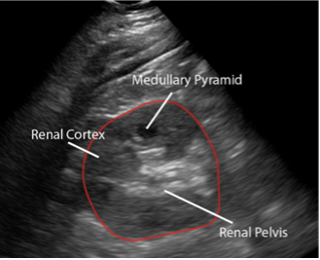

In the PLAX view, we see the interventricular septum (IVS), LV cavity, and the posterior wall of the LV (Figure 3). You should see the mitral valve, LV outflow tract, and AOV in one continuous plane. Most often, you will not see the distal ventricle/apex in the same window as your AOV/MV.

Figure 3: Parasternal long axis view in cardiology convention anatomically labeled.